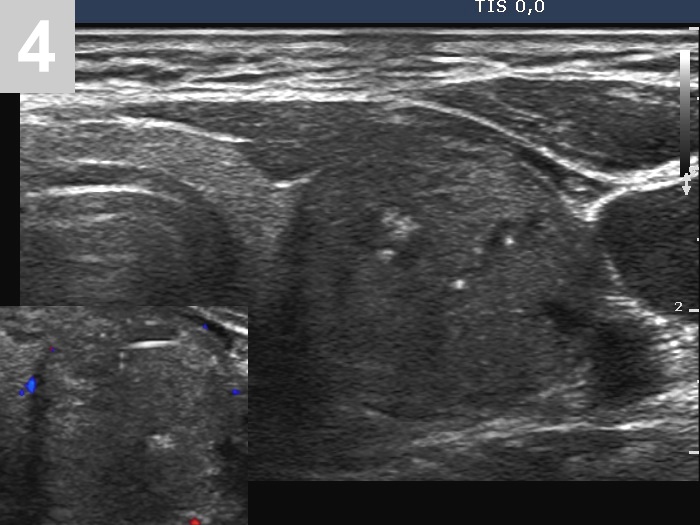

3 US of thyroid cancer

Pre- and postoperative ultrasound in thyroid cancers

Cases to be discussed on January 18, 2024